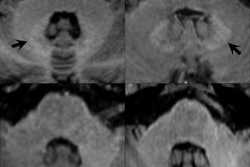

High-resolution T2-weighted (above) and enhanced T1-weighted (below) images of large intra- and extrameatal vestibular schwannoma. All images courtesy of Dr. Francesca Pizzini."Gadolinium-based contrast agents increase the relaxation rate of water protons in the region where they distribute, thus providing relevant information on pathologies, involving changes in the vascular density and permeability and structural differences," she said. "Unenhanced sequences available are not currently providing comparable and alternative structural details."